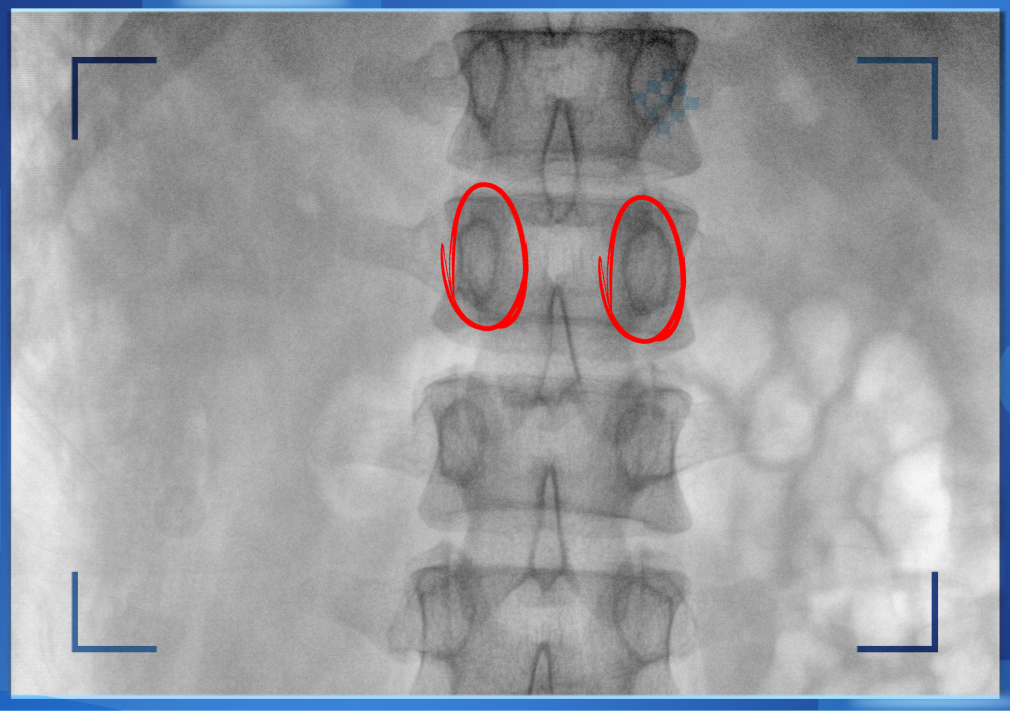

医生通常会在“猫眼”里寻找进针点和出针点,凭医生的经验把钉子打在椎弓根里。手术比较依赖医生的经验,万一出现偏差对病人来讲就是毁灭性的打击。如果在复杂的手术中有三维影像的支持,确保钉子精准的打在椎弓根里,可大大的提高手术操作的精度。

“猫眼”指的是椎弓根在正位的投影。